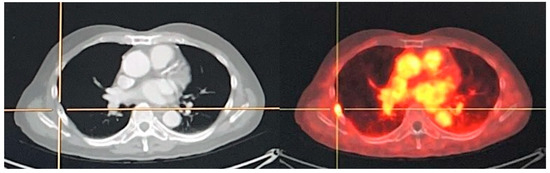

Figure 3.

An example of old rib fracture in a PCa patient who underwent radical prostatectomy and RT, developed rising serum PSA with a level of 0.375 ng/mL (nadir 0.1 ng/mL) was sent to evaluate BCR. 18F PSMA PET scan revealed faint uptake at lateral aspect of left 7th rib associated with subtle sclerotic lesion (SUVmax of 3.14).